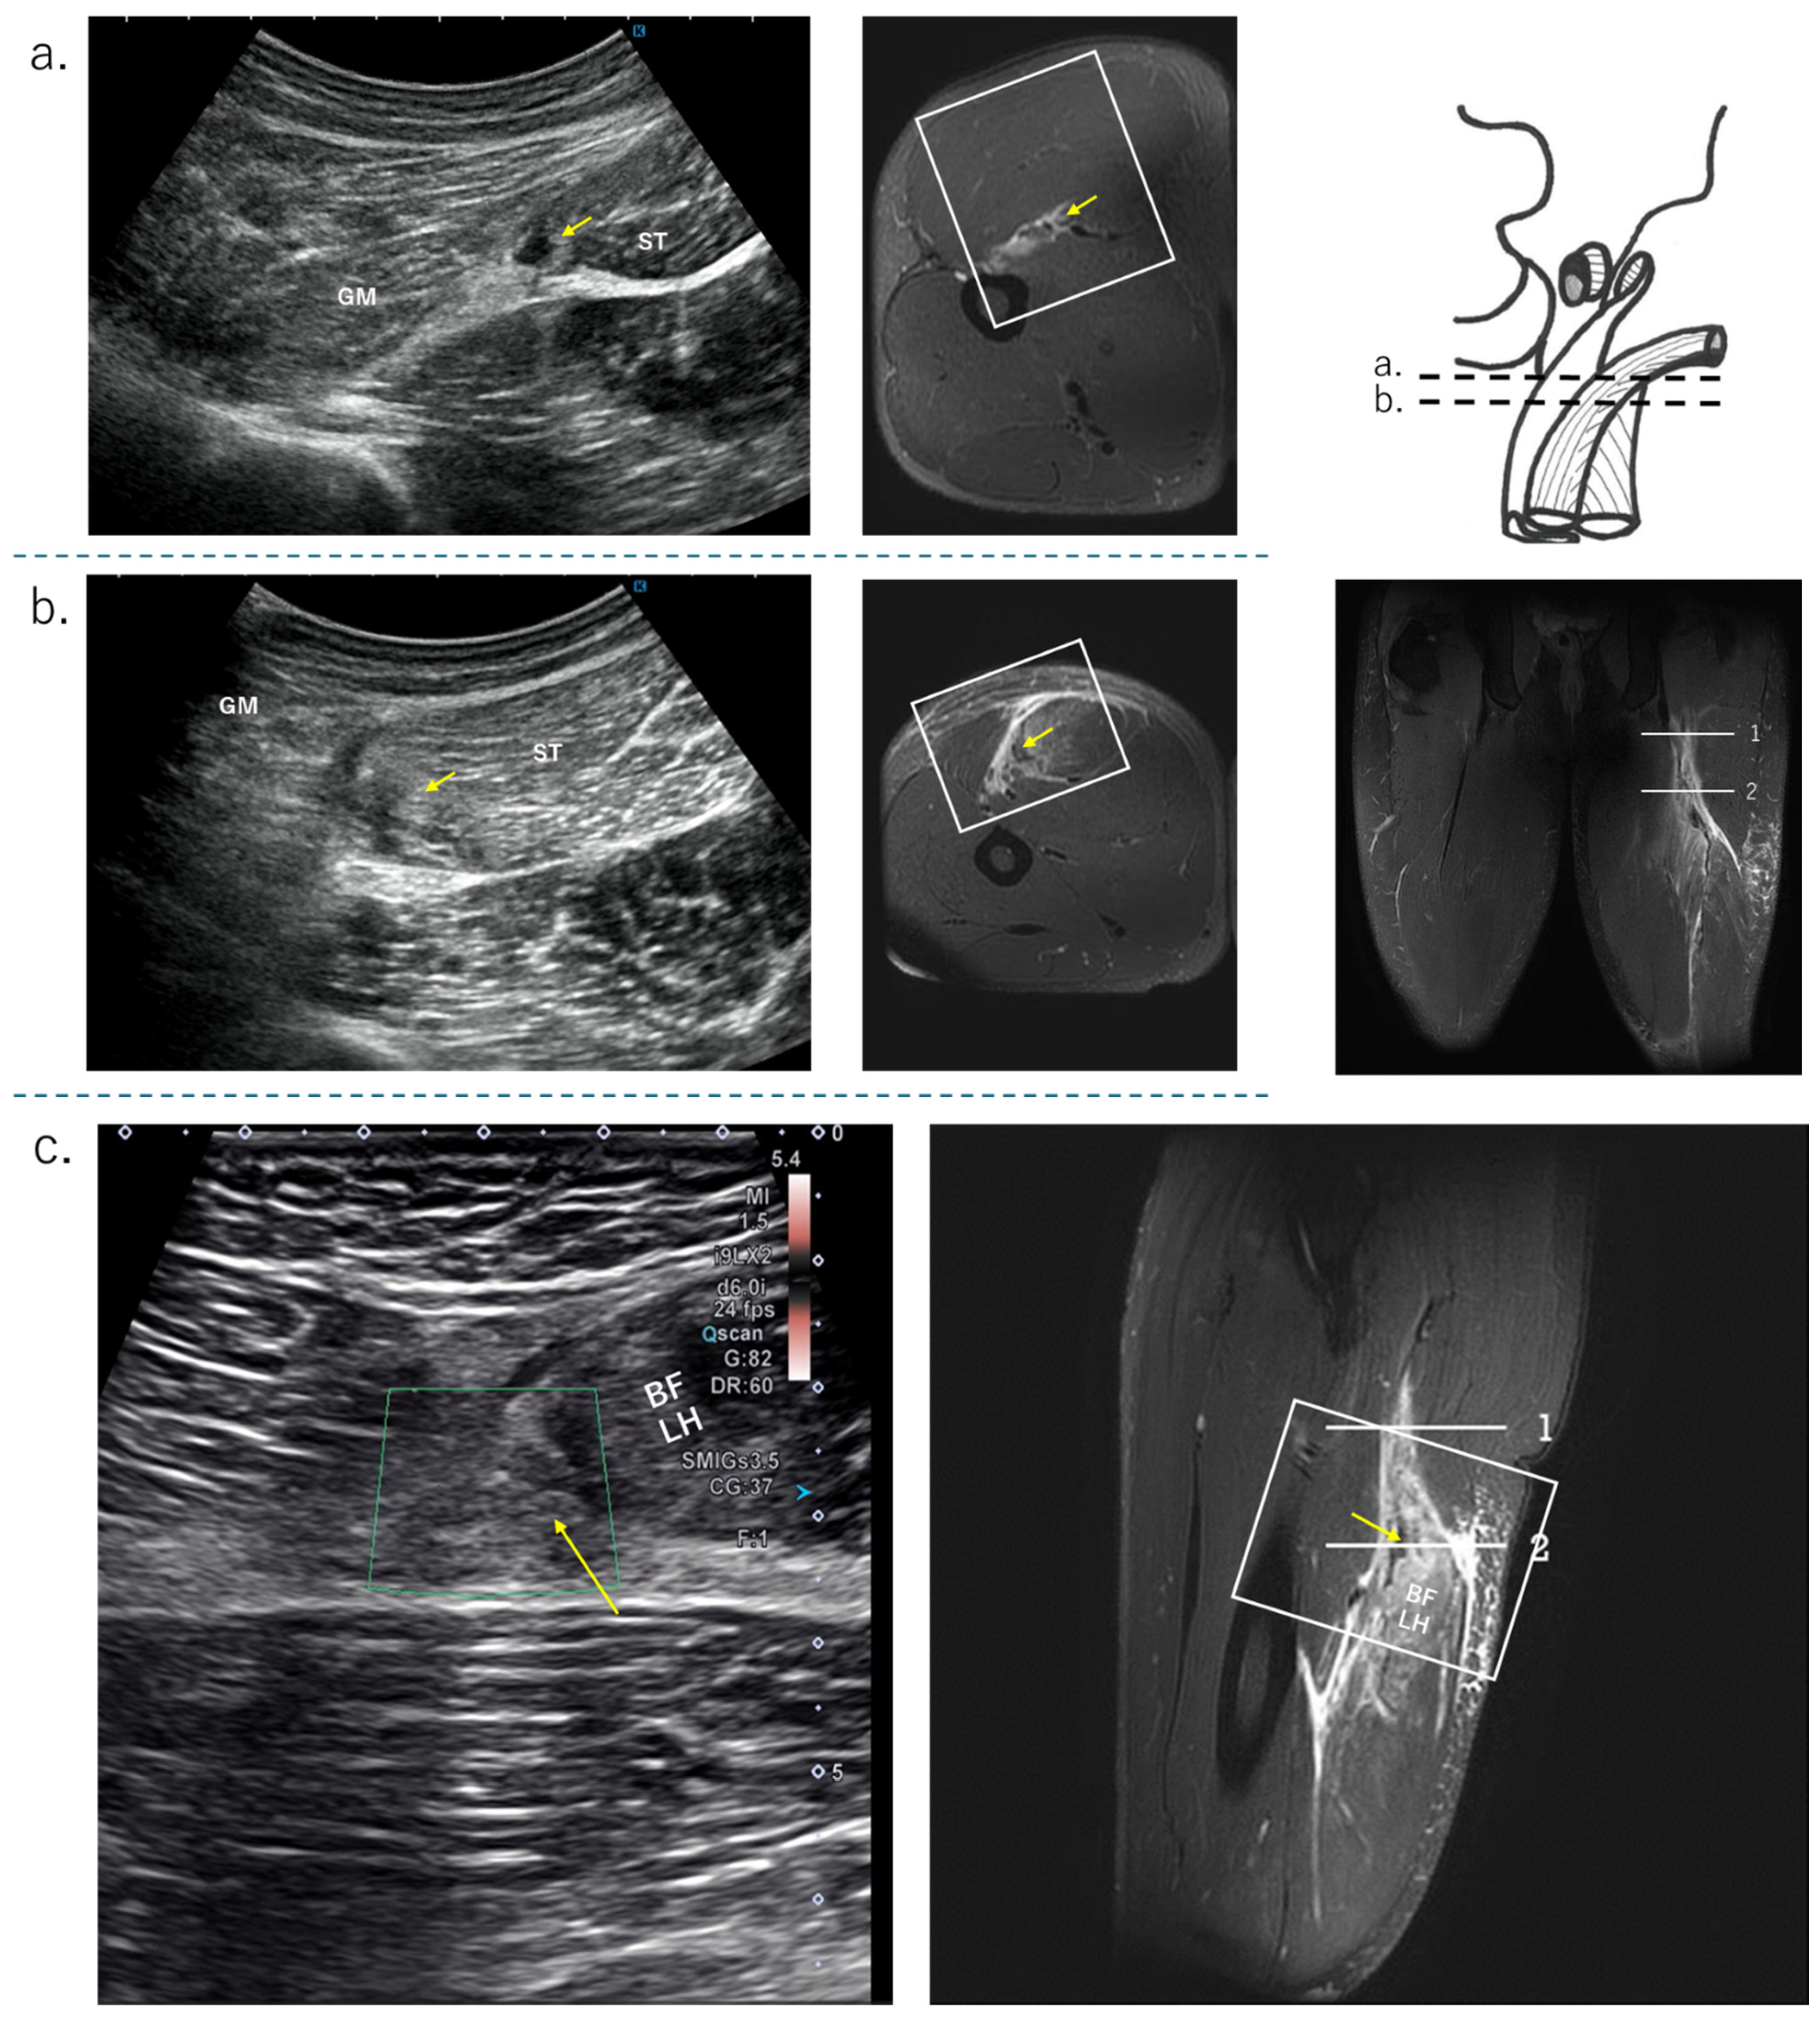

4.4. Biceps Femoris Tear

In this section, we will discuss injuries of the distal portion of the BFLH (Type II) and of the BFSH. The proximal MTJ of BFLH has a strong pennate structure. This part of the body is prone to muscle strain. Figure 7 shows an MTJ injury on the BFLH side of the CT. First, a hematoma is confirmed on the BFLH side of the CT in the short-axis image of the ultrasound, and the extent of the MTJ damage is confirmed in the long-axis image of the BFLH muscle fiber direction. A detailed evaluation of whether the damage has spread to the ST side of the CT is performed using MRI findings. There were three cases of slight damage to the fascia on the starting side of the MFJ, which was difficult to detect using US. There were five cases of intramuscular injury and injury to the aponeurosis within the muscle that is continuous with the distal fascia. There were also four cases of distal myofascial injury. The distal myofascial junction also has a pennate structure and is a common site for muscle tears. In this survey, there were no ruptures or avulsions of the distal tendon. Such slight MFJ injuries in BFLH often have no hematoma, are relatively deep, and may be difficult to delineate muscle fibers, resulting in low ultrasound detection (Table 3). The biceps femoris short head (BFSH) is a uniarticular muscle of the knee and is less frequently injured.

Figure 7. The US findings of proximal MTJ tear of BFLH. GM: gluteus maxim; SN: sciatic nerve, MRI condition: T2-weighted image with fat suppression; (a) long-axis view, no bending of the CT and hematoma on the BFLH side of the CT; refer to the coronal MRI image; (b) short-axis view, hematoma on the BFLH side of the CT (white arrow), but not on the ST side.